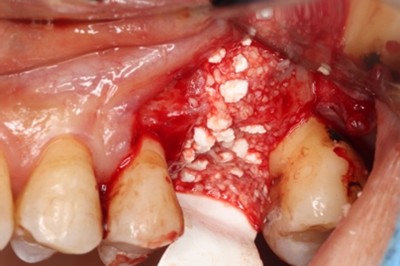

抜歯時に頬側の骨の大きな欠損を認めた。サイトランス®を使用したRidge Preservation、Cytoplast®※を使用し抜歯窩を被覆

骨の再生が起きており十分な骨幅を認める

破折歯を抜歯した場合、今回のケースのように骨の吸収が著しく生じていることが多く、このままではインプラント周囲に十分な骨幅(理想的にはプラットフォームから2mmの骨幅)を維持することができないためRidge Preservationは非常に有効な手法であると考える。